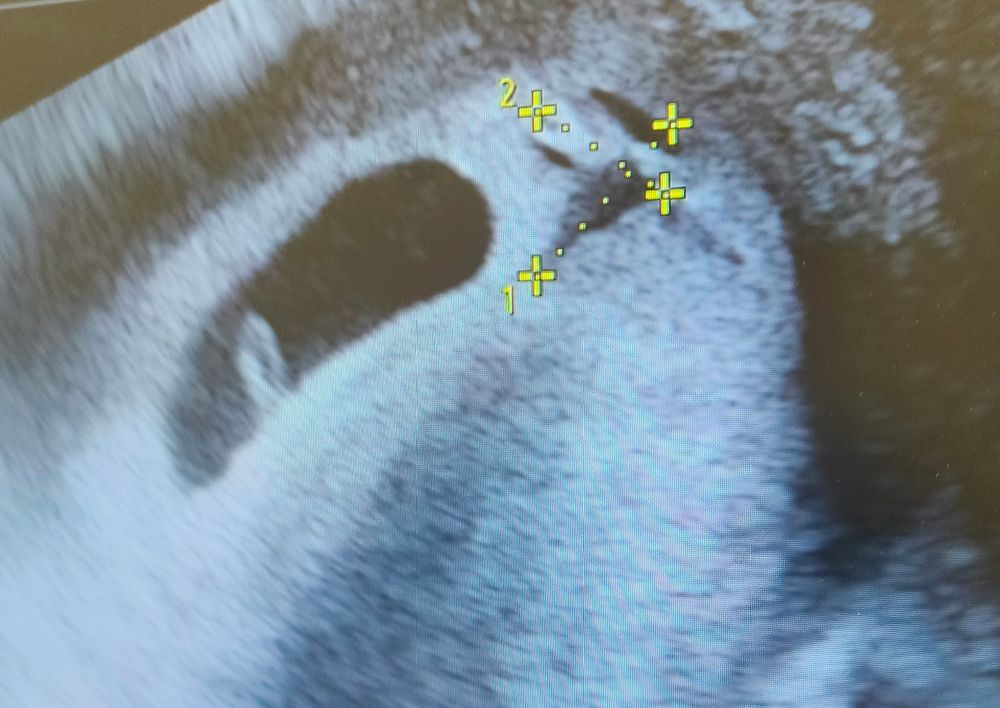

Лялечка в порядке, сердцебиение видно прям на экране, 160 в минуту. Правда, КТР намерили 8 мм, но может зависит от аппарата и узиста, не знаю.

Ну и рядышком гематом 11.4*8.9 мм, потому и мажет. Сказали, что ничего угрожающего эмбриону нет, надо просто попить Транексам, сходить к врачу и ждать, когда выйдет с концами.